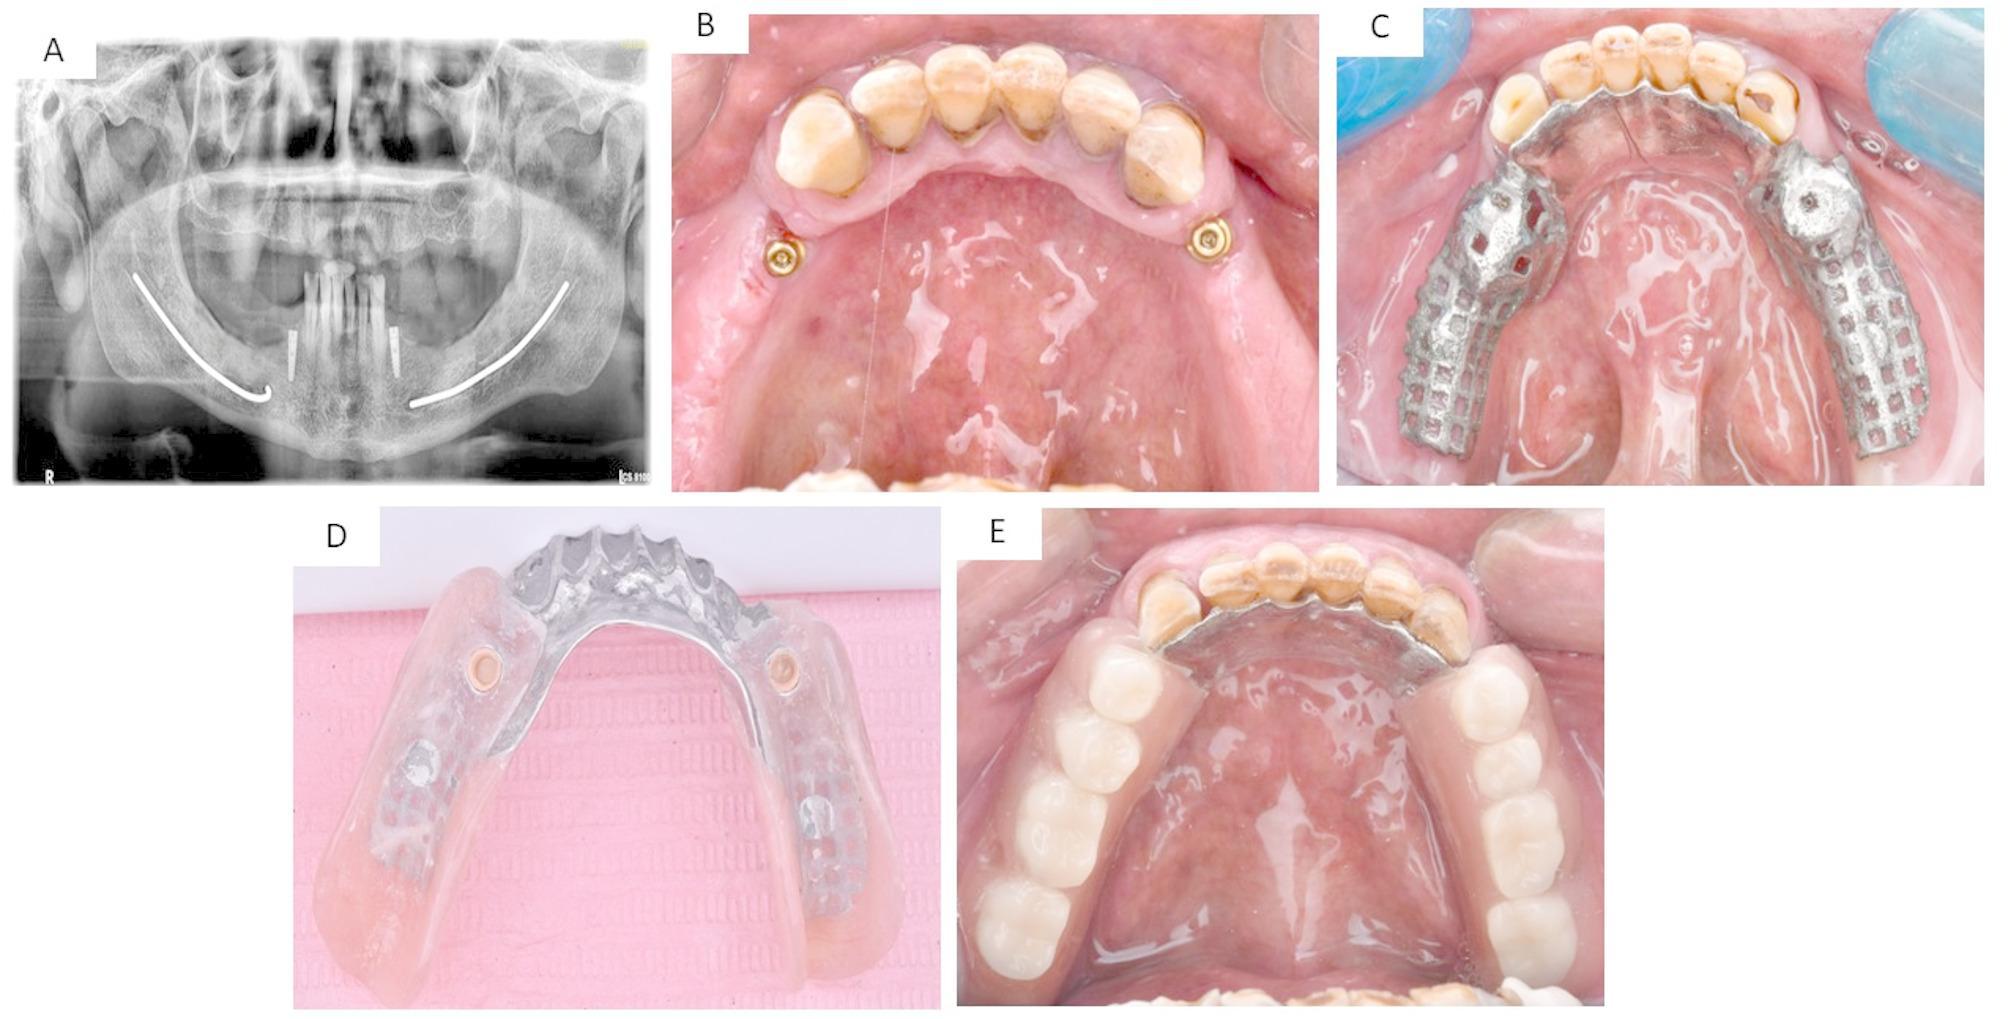

This study assessed the clinical outcomes of fixed and removable implant-assisted prostheses for the rehabilitation of atrophied distal extension mandibular ridges.

Thirty partially edentulous patients with atrophied distal extension mandibular ridges were randomized to three groups (n = 10/group). Group ALF received long implants following alveolar ridge augmentation to support fixed restorations. Group SF received short implants to support fixed restorations. Group OVD received two long implants to support a removable partial denture. The plaque index (MPI), gingival index (MGI), Pocket depth (PD), implant stability (IS), and crestal bone loss (CBL) were assessed: immediately after the prosthesis insertion (T0), six months (T6), and twelve months (T12) later. All groups were assessed for patient satisfaction after 12 months using a visual analogue scale (VAS) survey.

30例下颌远中延伸嵴萎缩的部分牙列缺损患者被随机分为三组(每组n = 10)。ALF组在牙槽嵴增高后植入长种植体以支持固定修复体。SF组植入短种植体以支持固定修复体。OVD组植入两颗长种植体以支持可摘局部义齿。评估菌斑指数(MPI)、牙龈指数(MGI)、牙周袋深度(PD)、种植体稳定性(IS)和嵴顶骨吸收(CBL):在修复体植入后即刻(T0)、6个月(T6)和12个月(T12)。12个月后使用视觉模拟量表(VAS)调查评估所有组患者的满意度。